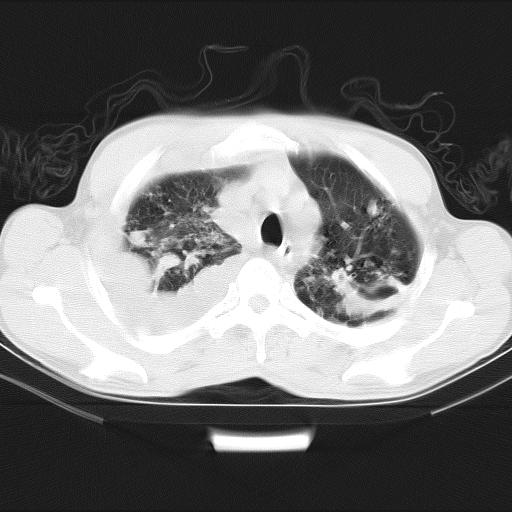

男性,44岁,结核病史多年。现胸闷气短,咳嗽,偶咳血。

1、右侧大量胸腔积液伴右肺压缩性膨胀不全,建议抽液治疗后复查 2、两肺继发性tb伴空洞形成。

1)两肺继发性肺结核伴空洞形成,左肺多发性结核球。2)右侧大量胸腔积液伴右肺部分膨胀不全。3)纵隔淋巴结肿大。

1,双肺多发结节 并空洞影改变, 左侧胸腔积液并部分包裹, 结合原病史首先考虑结核. 但也不除外其它.

2,左侧有一根肋骨陈旧性骨折? 建议追查 .